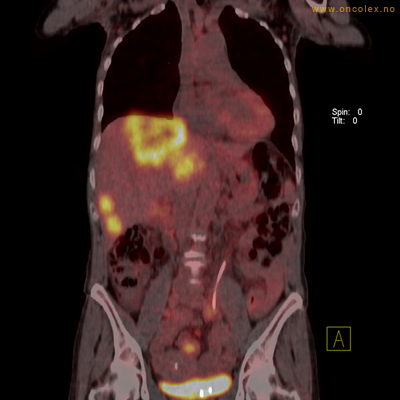

Eksempler på funn

Vev som tar opp mer radioaktivt stoff, synes som hvite områder som lyser opp mer i forhold til annet vev som tar opp mindre sukker.

Spredningssvulster til lever med sentral nekrose.